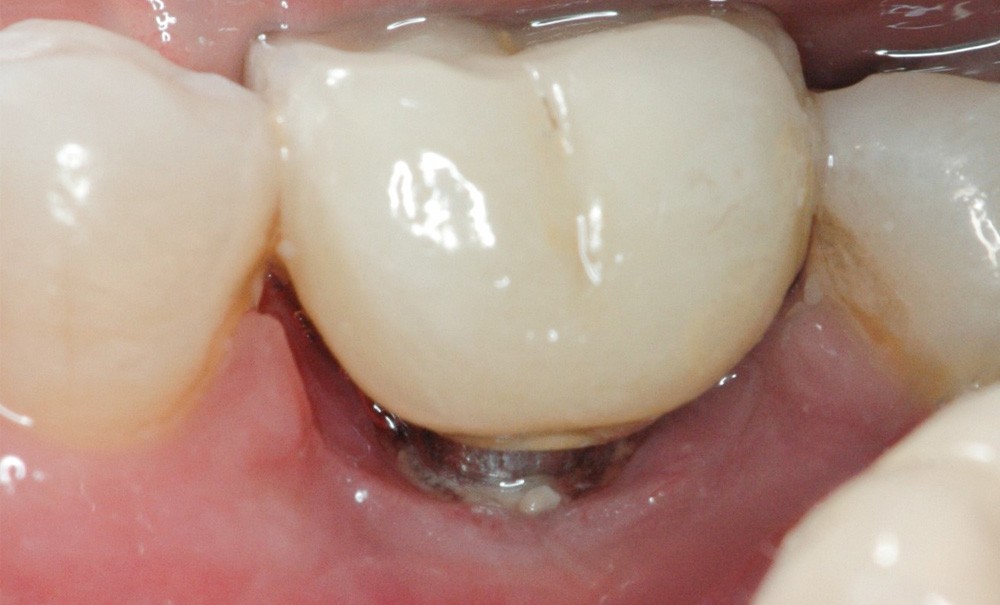

- Péri-implantite diagnostiquée en 2021

Chez ce patient, le traitement de la péri-implantite a comporté une chirurgie associant décontamination électrolytique de la surface implantaire, régénération osseuse guidée et enfouissement de l’implant. Le résultat à 2 ans est très moyen au vu du pourcentage de régénération osseuse obtenu. Comment peut-on prévoir un tel résultat alors que l’on a suivi les recommandations à la lettre, que l’on a utilisé les dernières technologies de décontamination, que l’on y a mis tous les moyens, que le patient est en bonne santé générale et qu’il vient en plus régulièrement aux séances de thérapeutique de soutien ? Le succès du traitement des péri-implantites n’est pas simple à obtenir, surtout quand un élément clé est compromis… la maintenance personnelle ! En effet le succès n’est possible que si le contrôle de plaque quotidien est optimal et, ici, ça n’était pas le cas. Le patient se brossait certes les dents, mais ne passait pas quotidiennement les brossettes, ce qui…